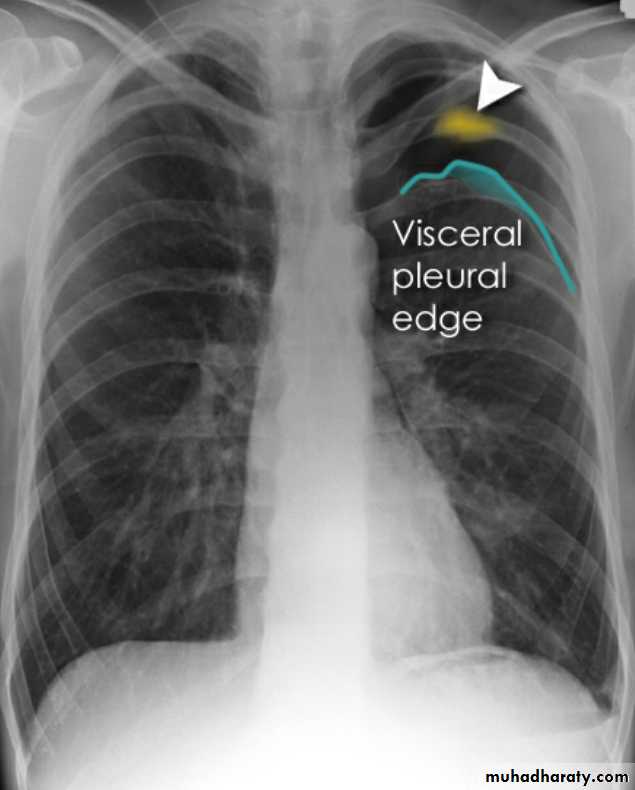

Pneumothorax

Pneumothorax refers to the presence of gas (air) in the pleural space. When this collection of gas is constantly enlarging with resulting compression of mediastinal structures it can be life-threatening and is known as a tension pneumothoraxIt is useful to divide pneumo thoraces into three categories :

Chest radiograph

A pneumothorax is, when looked for, usually relatively easily appreciated. Typically they demonstrate:

visible visceral pleural edge see as a very thin, sharp white line

no lung markings are seen peripheral to this line

the peripheral space is radiolucent compared to adjacent lung

the lung may completely collapse

the mediastinum should not shift away from the pneumothorax unless a tension pneumothorax is present